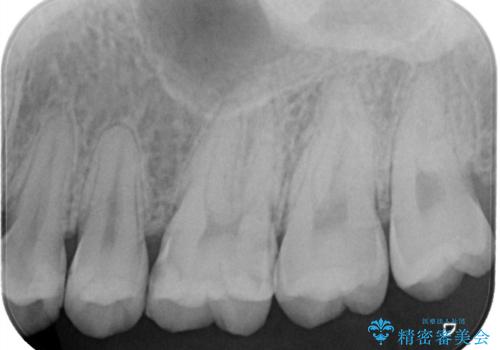

- 冷たいものがしみるとご相談に来られた患者様です。一見、外からではわかりづらい部分に深めの虫歯を認めたため、神経保護の意味合いも兼ねて即日にてセラミック修復を行いました。術後も経過良好です。